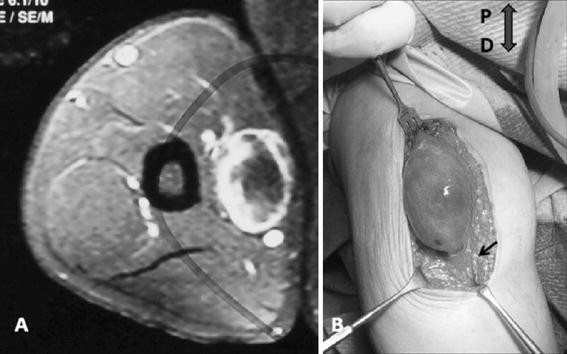

a Axial view, fat suppressed with gadolinium. Round lesion well circumscribed with enhancement of the periphery. bOval shaped capsulated mass in eccentric position along the median nerve (arrow). P proximal; D distal

In our case, the cystic areas involved a higher percentage compared to the viable tumor on an axial view. On MRI the viable tumor areas were enhanced after gadolinium administration and, because of their peripheral location, a bright ring surrounded the nonenhancing irregular central cystic areas.